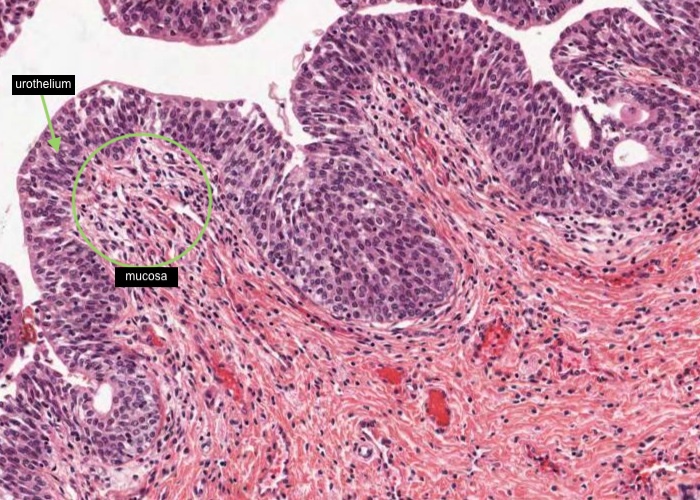

The mucosa has longitudinal folds which you may now appreciate better if you relook at the low magnification image in the previous item. The epithelium of the urethra will vary according to the region from which a section is taken. In this image, taken near the bladder, it is urinary/transitional epithelium (urothelium), at the external opening it is stratified squamous epithelium, and between those two ends the epithelium is pseudostratified or stratified columnar.

Small outpocketings of mucus-secreting cells form clusters in the epithelium and extend into the lamina propria as simple paraurethral glands. Those located within the epithelial layer are examples of intra-epithelial glands.